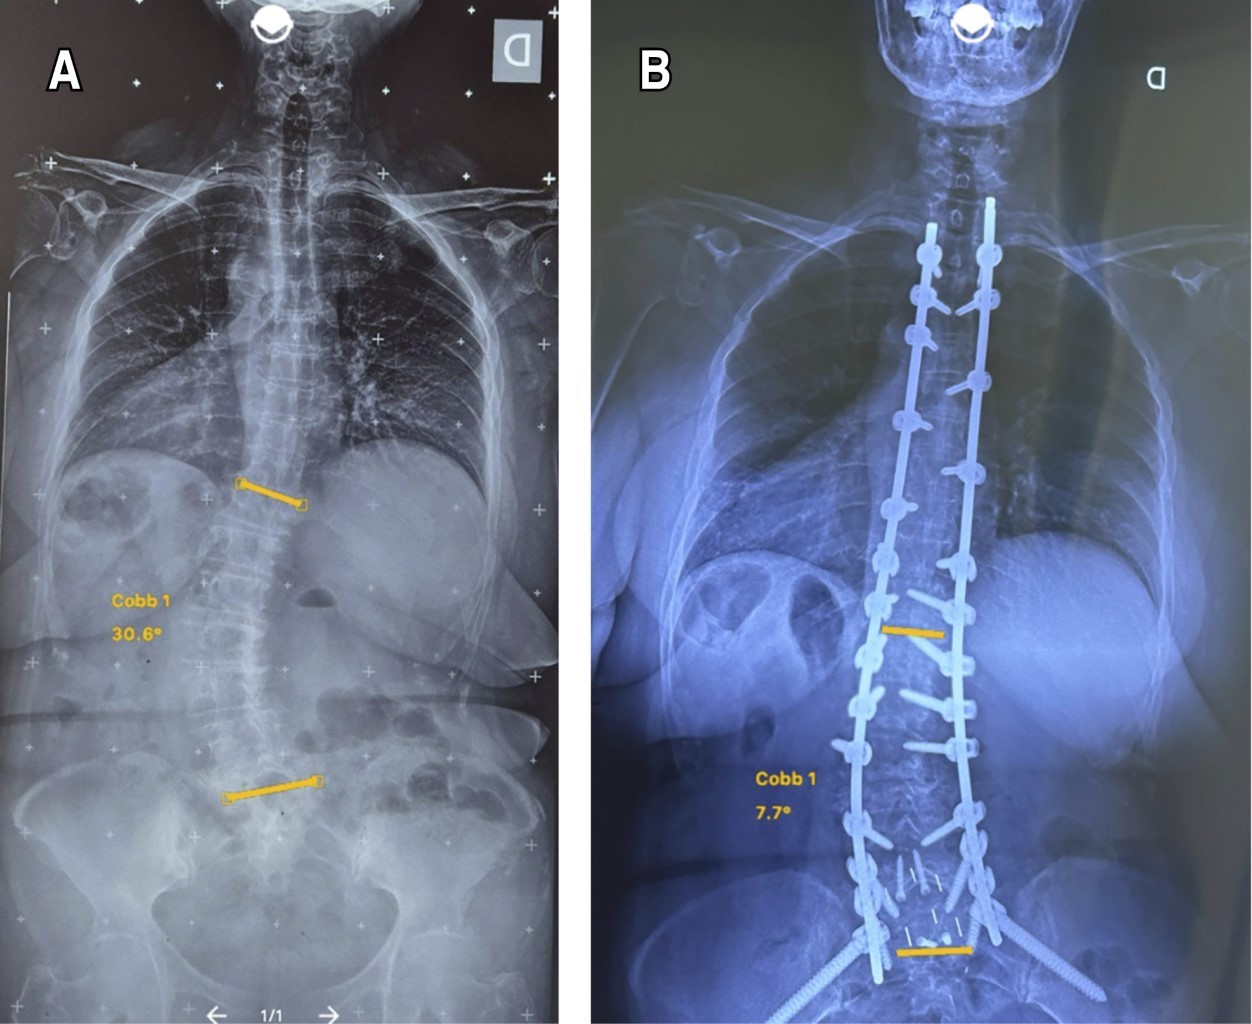

Figure 1